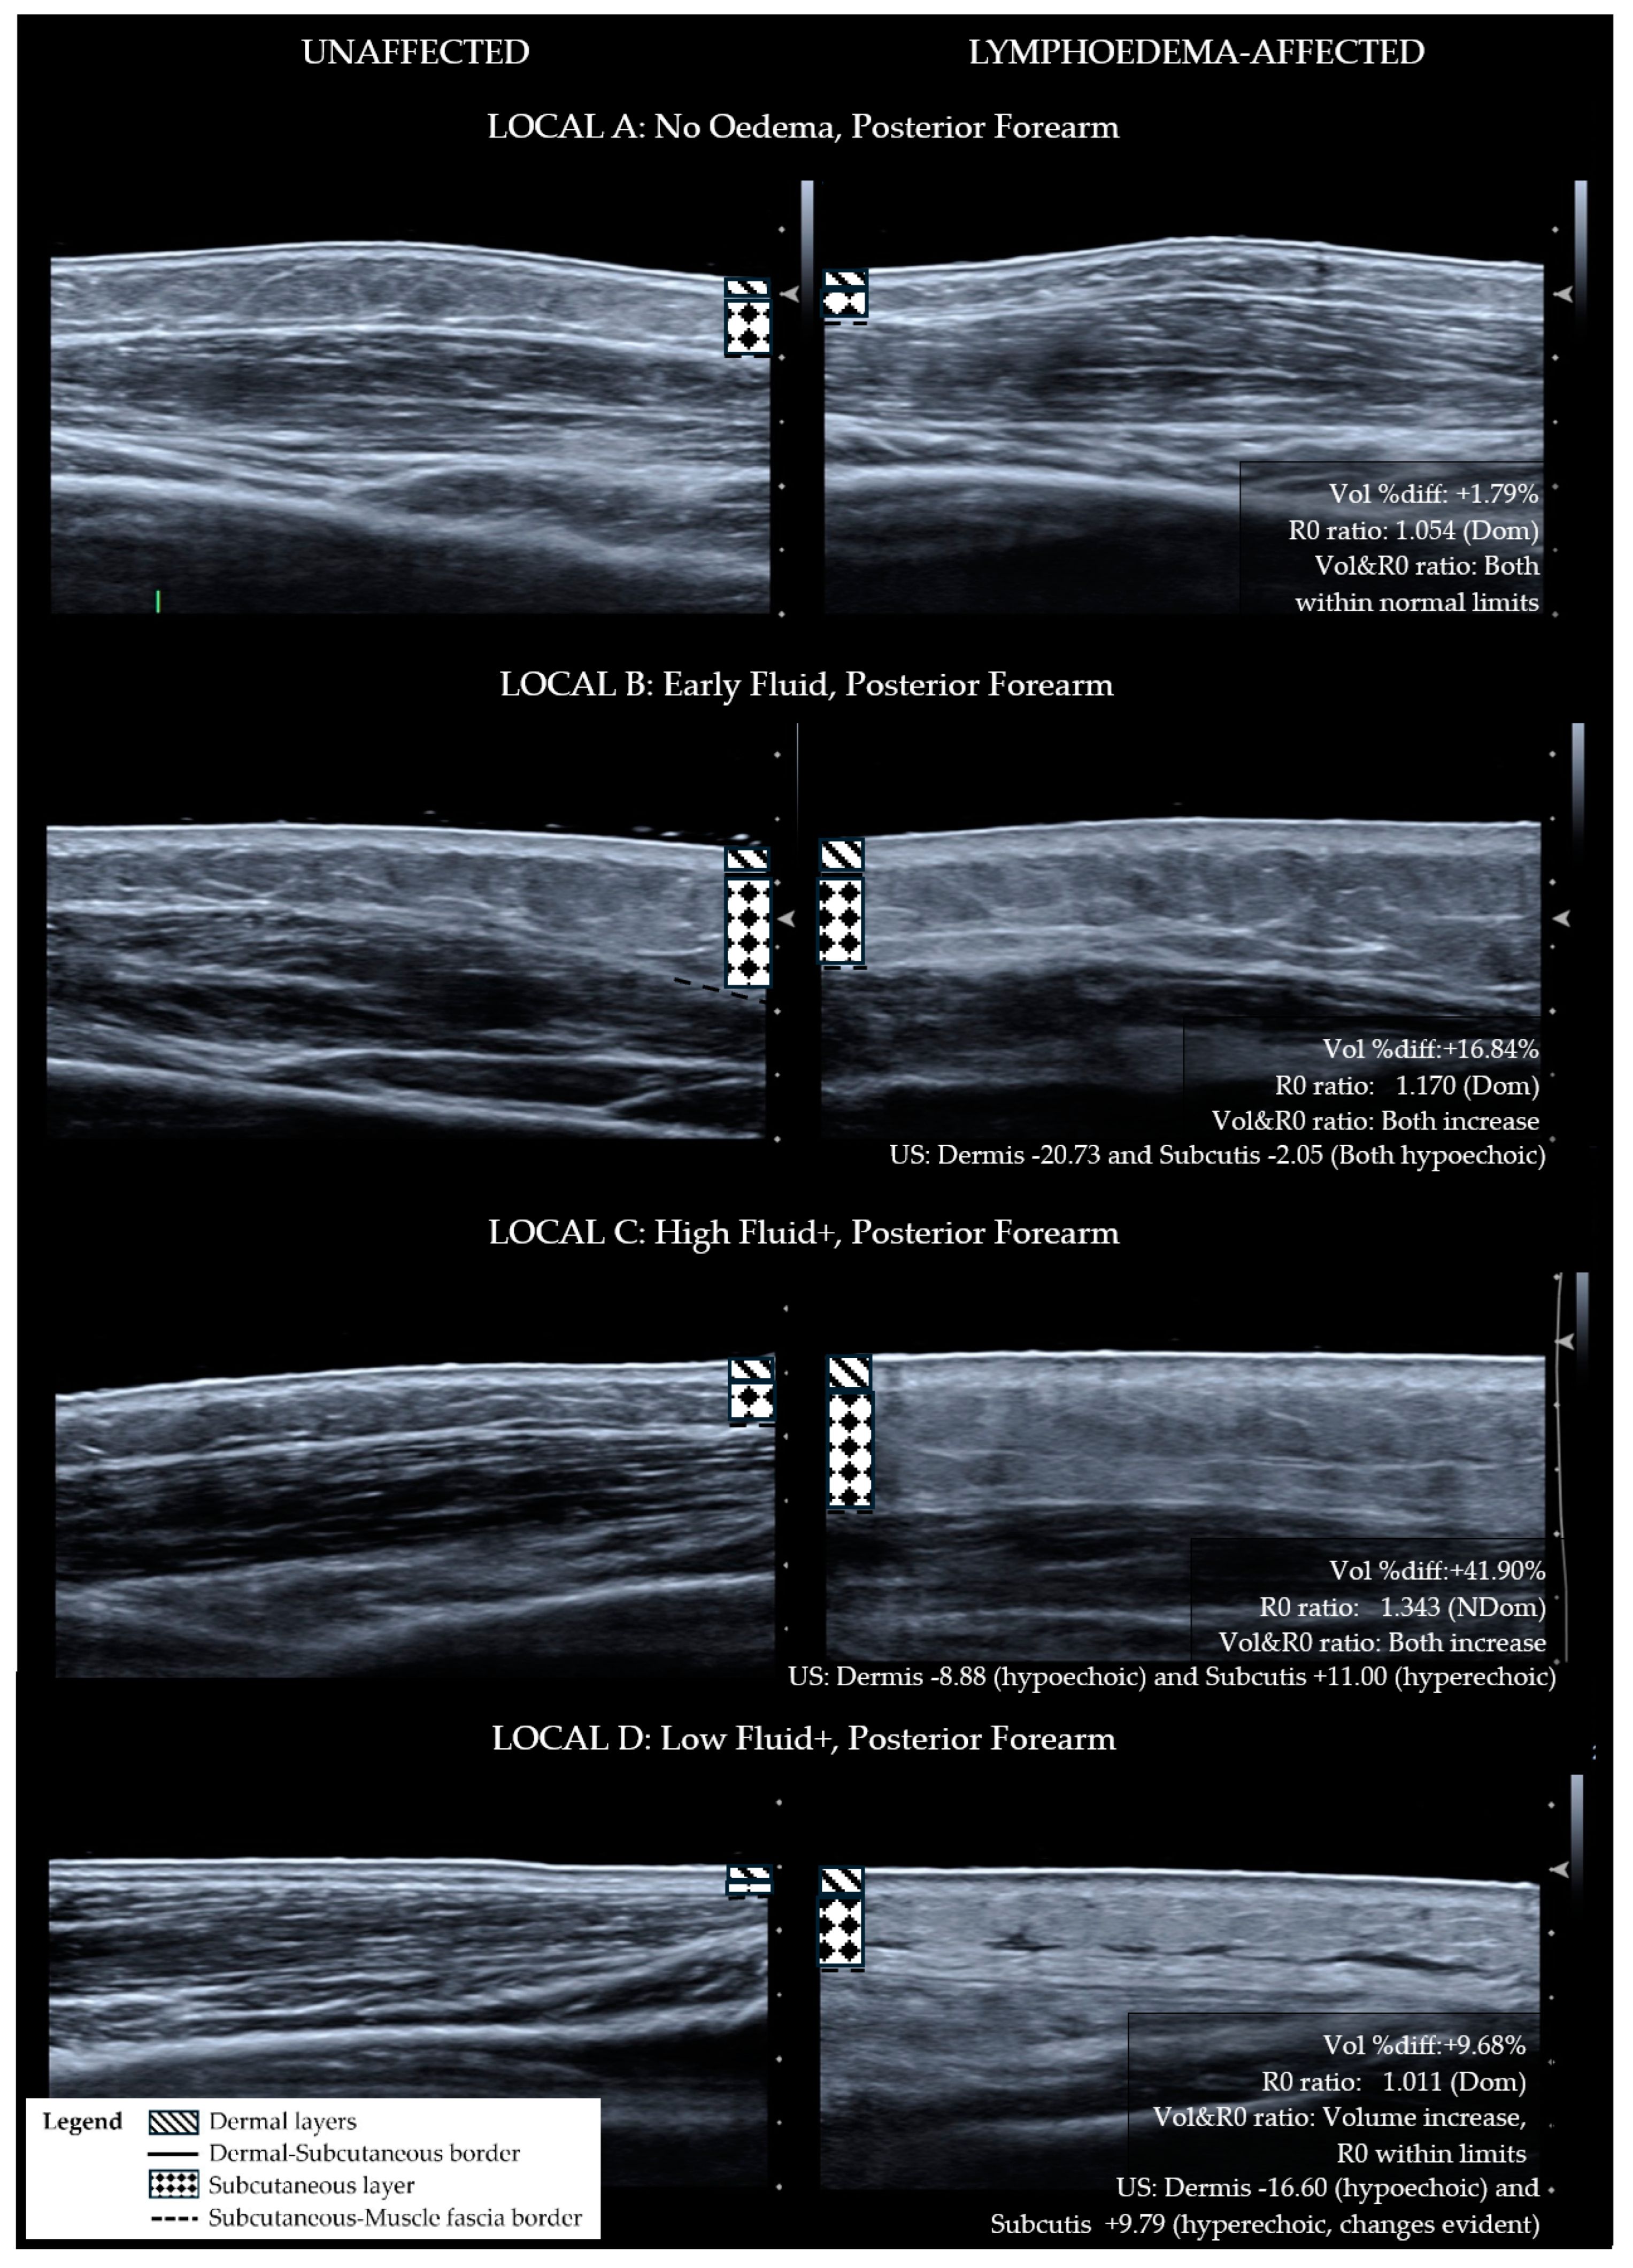

- The ultrasound echogenicity parameter is used to support the presence or absence of tissue compositional change. Lymphoedema tissue has been shown to become hypoechoic (darker) with diffuse fluid influx [15,16] and hyperechoic (lighter) with fibrotic and fatty deposition [17,18,19]. The distribution of hyper-echogenicity may encompass the full or partial cross-section of the tissue layer or appear as scattered flecks [17,18,19]. For this reason, a decrease in the echogenicity of the lymphoedema tissue layers was observed as fluid influx, and an increase in echogenicity escalated the classification to the fibro-fatty groupings.

| A No Oedema | B Early Fluid | C High Fluid+ | D Low Fluid+ |

|---|---|---|---|

| Site does not exhibit lymphoedema characteristics | Tissue exhibits extracellular fluid increase without compositional changes | Tissue exhibits fibro-fatty changes with high fluid volume | Tissue exhibits fibro-fatty changes with low fluid volume |

| Volume- Inter-limb segment difference (% difference between lymphoedema to non-lymphoedema segment) OR Limb segment change (% change from baseline) | |||

| Within normal limits Inter-limb segment: <5.0% (Dom) <3.0% (NDom) OR Limb segment change: <3.0% | May or may not meet inter-limb threshold. OR Exceeds threshold for limb segment change: ≥3.0% | Greater than normal limits Inter-limb segment: ≥5.0% (Dom) ≥3.0% (NDom) OR Limb segment change: ≥3.0% | Greater than normal limits Inter-limb segment: ≥5.0% (Dom) ≥3.0% (NDom) OR Limb segment change: ≥3.0% |

| BIS R0- Inter-limb segment ratio (Unaffected/Affected) | |||

| Within normal limits Forearm: ≤1.1385 (Dom) ≤1.0700 (NDom) Upper Arm: ≤1.1335 (Dom) ≤1.0915 (NDom) | Greater than normal limits Forearm: >1.1385 (Dom) >1.0700 (NDom) Upper Arm: >1.1335 (Dom) >1.0915 (NDom) | Greater than normal limits Forearm: >1.1385 (Dom) >1.0700 (NDom) Upper Arm: >1.1335 (Dom) >1.0915 (NDom) | Within normal limits Forearm: ≤1.1385 (Dom) ≤1.0700 (NDom) Upper Arm: ≤1.1335 (Dom) ≤1.0915 (NDom) |

| Volume and R0 relationship | |||

| Both within normal limits | Both exceed thresholds OR R0 ratio increase and volume decrease, e.g., muscle atrophy or musculoskeletal cause | Both exceed thresholds | Both exceed thresholds. Disproportionate change, i.e., physical volume change large and R0 ratio relatively small OR Opposing direction of change, e.g., volume increase AND R0 ratio less than 1.000 |

| Ultrasound Echogenicity—Lymphoedema API compared to Non-lymphoedema API | |||

| N/A | Dermis: Hypoechoic AND Subcutis: Hypoechoic | Dermis: Hyperechoic OR Subcutis: Hyperechoic | Dermis: Hyperechoic OR Subcutis: Hyperechoic |

| LOCAL Category | Anterior Forearm n (%) | Posterior Forearm n (%) | Upper Arm n (%) |

| A. No Oedema | 1 (6.6) | 1 (6.6) | 4 (26.7) |

| B. Early Fluid | 6 (40.0) | 4 (26.7) | 3 (20.0) |

| C. High Fluid+ | 4 (26.7) | 6 (40.0) | 4 (26.7) |

| D. Low Fluid+ | 4 (26.7) | 4 (26.7) | 4 (26.7) |

| Total (n) | 15 (100) | 15 (100) | 15 (100) |